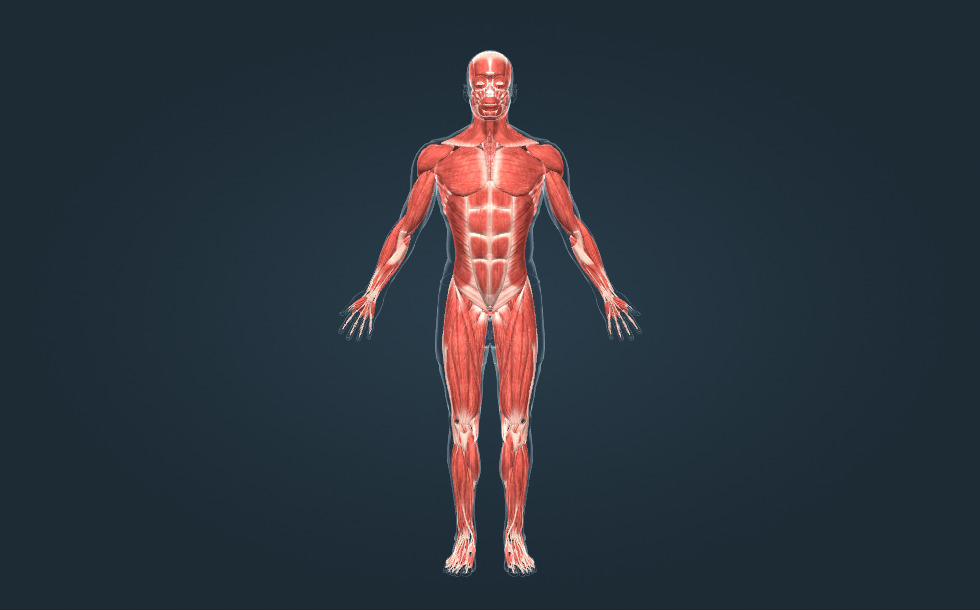

Skeletspieren

- spieren van het hoofd

- borstspieren

- buikspieren

- kuitspieren

- nekspieren

- spieren van de bovenarm

- spieren van de onderarm

- dijspieren

- rugspieren

De skeletspieren vormen de primaire bewegingsorganen. Er bevinden zich ongeveer 350 skeletspieren in het menselijk lichaam. Deze vormen dan ook ongeveer 50% van de totale lichaamsmassa. Er zijn lange, korte, platte en ringvormige spieren. Spieren zijn aan de botten verbonden door pezen.

De skeletspieren vormen de primaire bewegingsorganen. Er bevinden zich ongeveer 350 skeletspieren in het menselijk lichaam. Deze vormen dan ook ongeveer 50% van de totale lichaamsmassa. Er zijn lange, korte, platte en ringvormige spieren. Spieren zijn aan de botten verbonden door pezen.